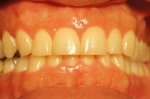

ホワイトニング1日・歯茎の漂泊一回

カメラ条件が違うので色はわかりずらいですが、オフィスホワイトニング1日・歯茎のレーザー漂白一回。ホワイトニングの効果に関しては一枚目と二枚目を比較して見てください。三枚目は歯茎の漂泊前、四枚目は歯茎の漂泊後です。レーザーで焼くので2~3日二枚目の写真のようなカサブタが出来てしまいますが痛みはありません。